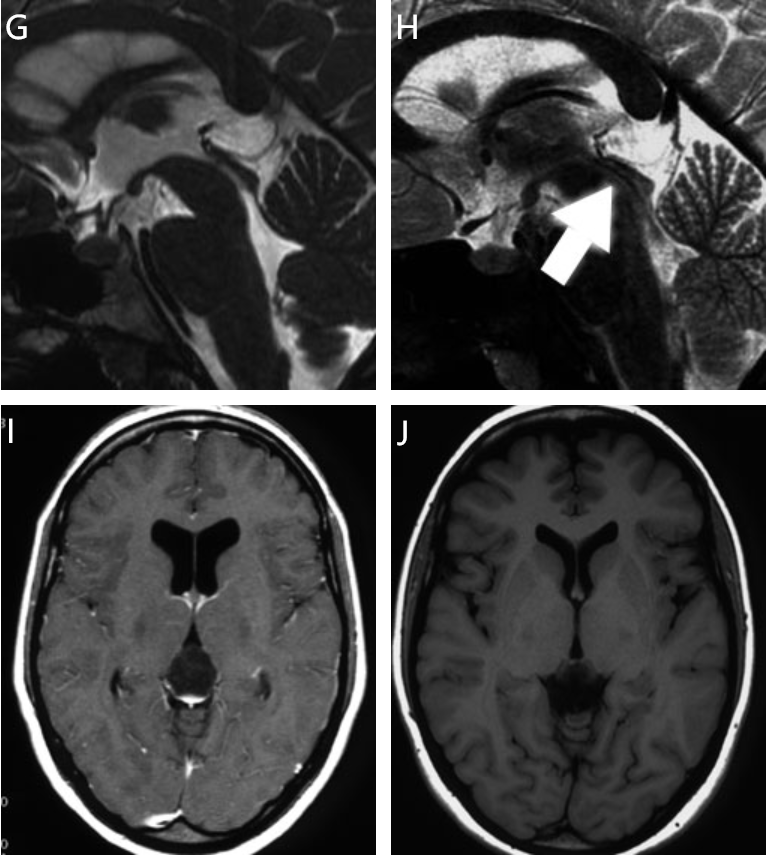

症状表现大多数松果体囊肿无症状,常在头颅磁共振成像MRI或计算机断层扫描CT检查中偶然发现若囊肿体积较大,可能压迫周围脑组织或阻塞脑脊液循环通路,引发头痛恶心呕吐等症状儿童患者还可能出现性早熟发育迟缓等生殖系统或生长发育异常,需高度警惕诊断与监测诊断主要依赖影像学检查,MRI可。